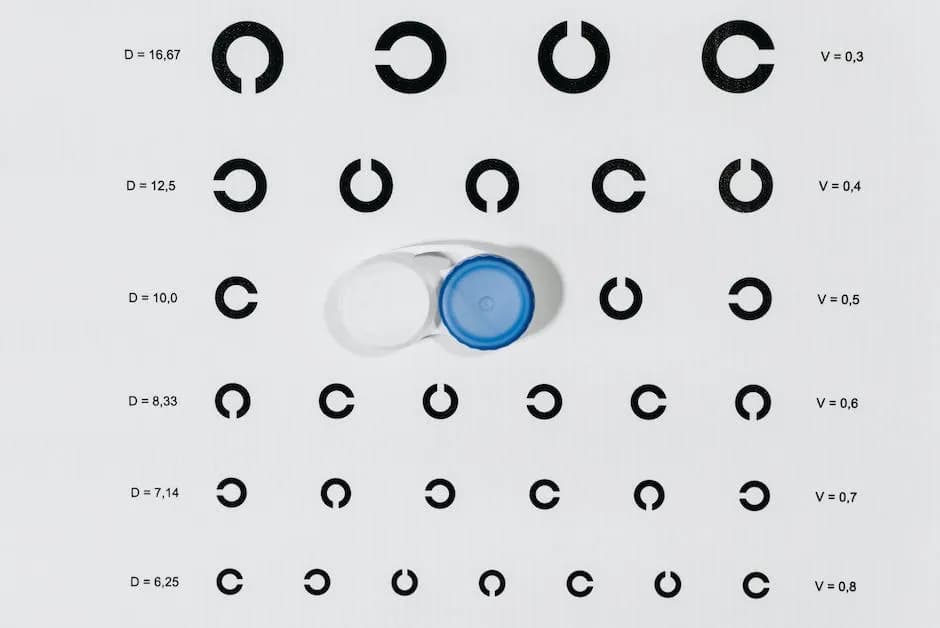

Szkła kontaktowe

Jak działają soczewki progresywne - sekrety komfortowego widzenia w każdej odległości

Poznaj zasadę działania soczewek progresywnych i ich strefy widzenia. Dowiedz się jak się przyzwyczaić do nowych soczewek i zapewnić sobie komfort widzenia na każdą odległość.